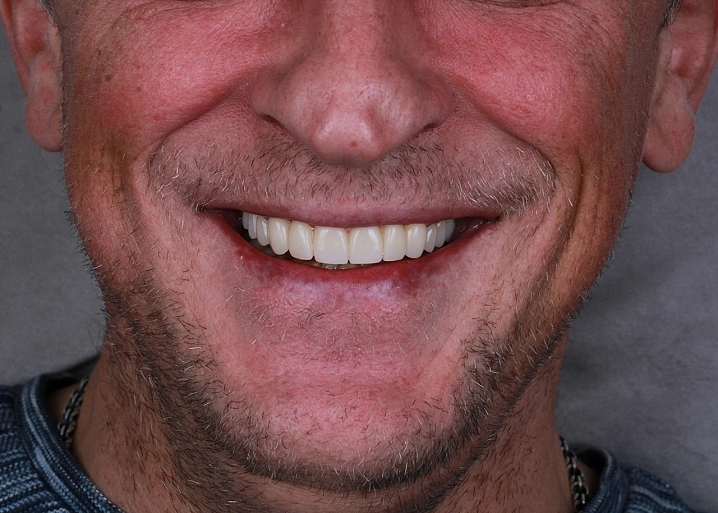

Проведена полная эстетическая реставрация зубных рядов верхней и нижней челюстей винирами E-max. Восстановлена форма, размер, цвет и поверхность фронтальных зубов, достигнута гармоничная улыбка.

Проведена эстетическая реставрация передних зубов верхней и нижней челюстей винирами E-max. Исправлены форма, размер и восстановлена поверхность зубов.

Пациент прошел комплексную диагностику и 3D моделирование улыбки. После этого были изготовлены и установлены керамические виниры E-max, что позволило добиться гармоничного и естественного вида зубов.